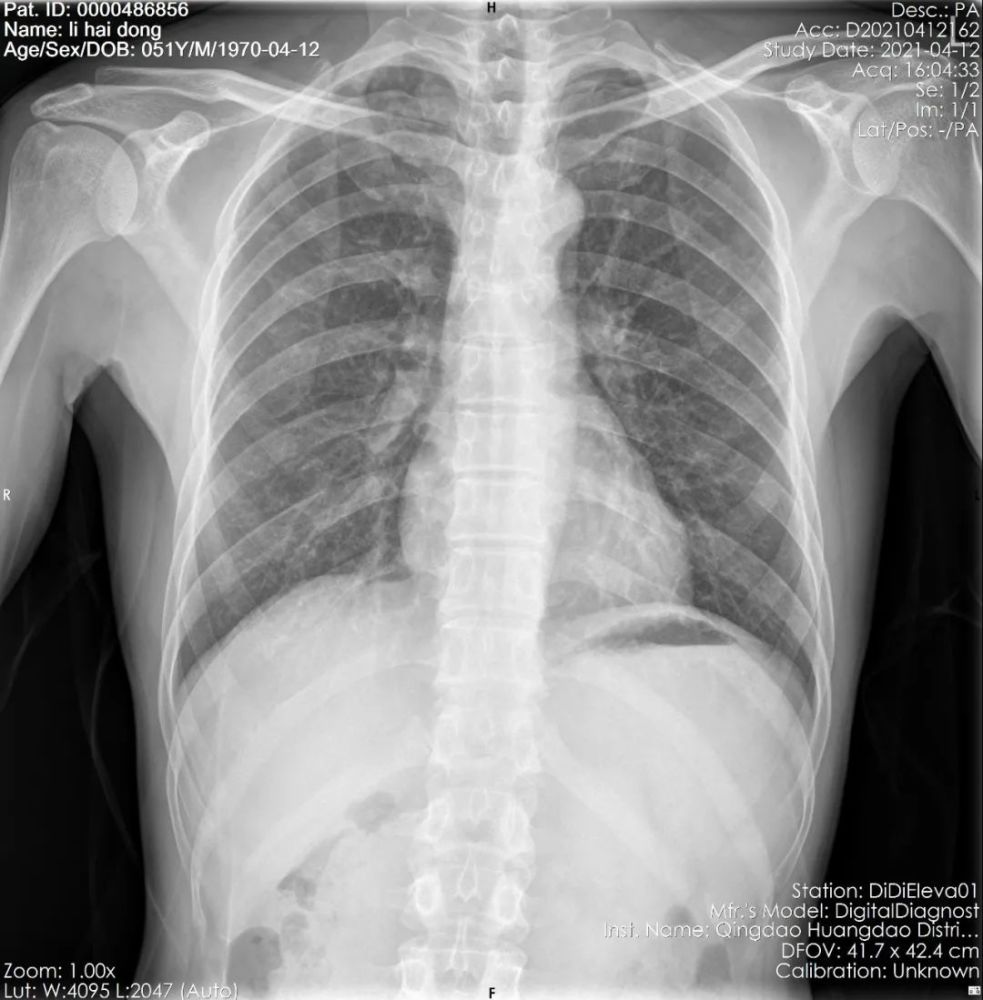

肋骨骨折什么症状 肋骨骨折主要的症状是胸痛,尤其是肋骨受伤的部位,局部的按压痛会非常的明显。 除了按压以外,病人如果在咳嗽、活动或者深呼吸的时候,也会明显的感觉到胸痛,这时候只有静止才能缓解。 如果骨折引起了肺破裂,引起了气胸,血胸 肋骨骨折是一种相当常见的损伤,包括或多或少严重的胸肋骨折 通常骨折只影响一根肋骨; 然而,在特别不幸的情况下,它会同时影响多个相邻的肋骨(多根肋骨骨折) 最常发生骨折的肋骨是位于肋骨中心的肋骨。 上肋骨(第一和第二)骨折通常发生在面部肋骨骨折 肋骨骨折とは、胸部を取り囲む骨にひびが入ったり骨が折れたりすることです。 肋骨骨折は重度の痛みを引き起こし、特に深呼吸したときに痛みがひどくなります。 通常は胸部X線検査が行われます。 痛み止めを投与され、肺の病気を予防する

肋骨骨折症状诊断 (一)、症状 1、在腋窝部的第6~9肋。 当肋骨本身有病变时,如原发性肿瘤或转移瘤等,在很轻的外力或没有外力作用下亦可发生肋骨骨折,称为病理性肋骨骨折。 2、肋骨骨折多发生在 3章:肋骨骨折の後遺症②神経症状 肋骨骨折で、 変形障害は残らなかったものの骨折した所に痛みやしびれが残ってしまう 場合もあります。 この場合、「神経症状」という症状で後遺障害等級が認定される場合があります。